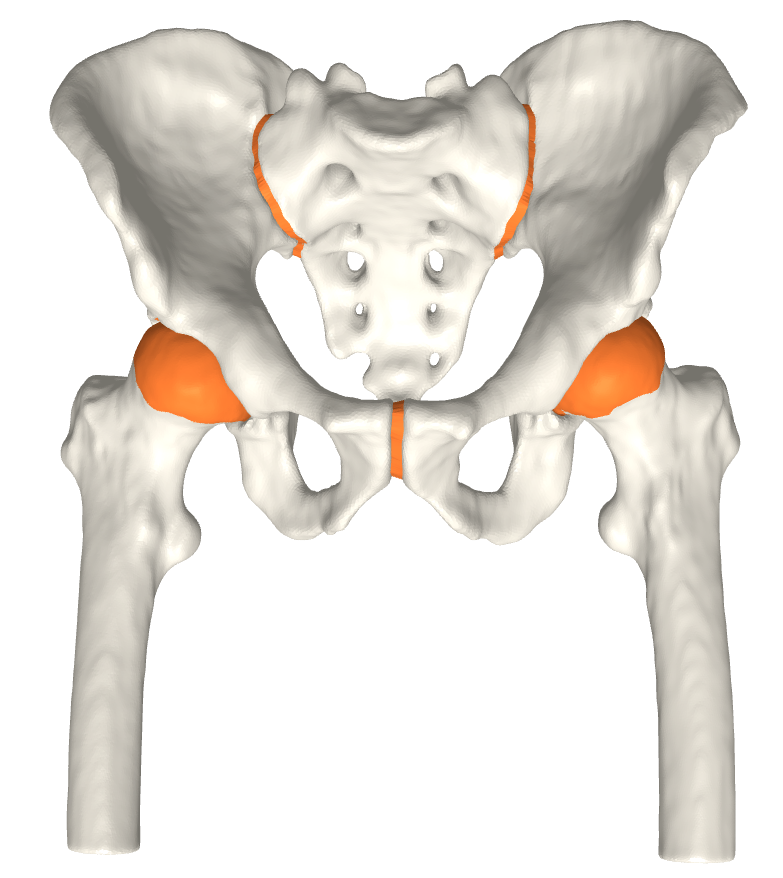

(c) Pelvic cartilage.

Figure 3: The final cartilage generated by our method for a femur (a), (b) and a pelvis (c). Notice how the cartilage aligns with the anatomical lines.

We have qualitatively verified that the articulating surfaces in all the ten HJs are detected correctly regardless of their anatomical variance using visual inspection of overlays as shown in Fig. 4. As desired, we observe a high degree of congruence between the opposing joint surfaces, meaning no gaps or overlaps in the cartilage-cartilage interface. Moreover, we observe a smooth transition towards the bone geometries as expected from the correct anatomy. The parameter values used to generate the cartilage from Fig. 5(a). The free parameters are the neighbourhood-size used to estimate the curvature of the bone (𝒩𝒩\mathcal{N}); the minimum and maximum curvature in the cartilage region (κmin,κmaxsubscript𝜅subscript𝜅\kappa_{\min},\kappa_{\max}; Eq. (2)); the distance parameter in mm𝑚𝑚mm (δ𝛿\delta; Eq. 1); and the number of times the outer boundary should be trimmed (Ntrimsubscript𝑁𝑡𝑟𝑖𝑚N_{trim}). Here, the curvature based parameters (𝒩,κmin,κmax)\mathcal{N},\kappa_{\min},\kappa_{\max}) are only used for the femur. See supplementary material for more visual comparisons.

(b) CT scan overlay.

Figure 4: The von Mises stress patterns ((a)) and the generated cartilage imposed on the CT scan from which the bone was extracted ((b)). Notice the high level of congruence in the cartilage-bone interfaces and cartilage-cartilage interface.